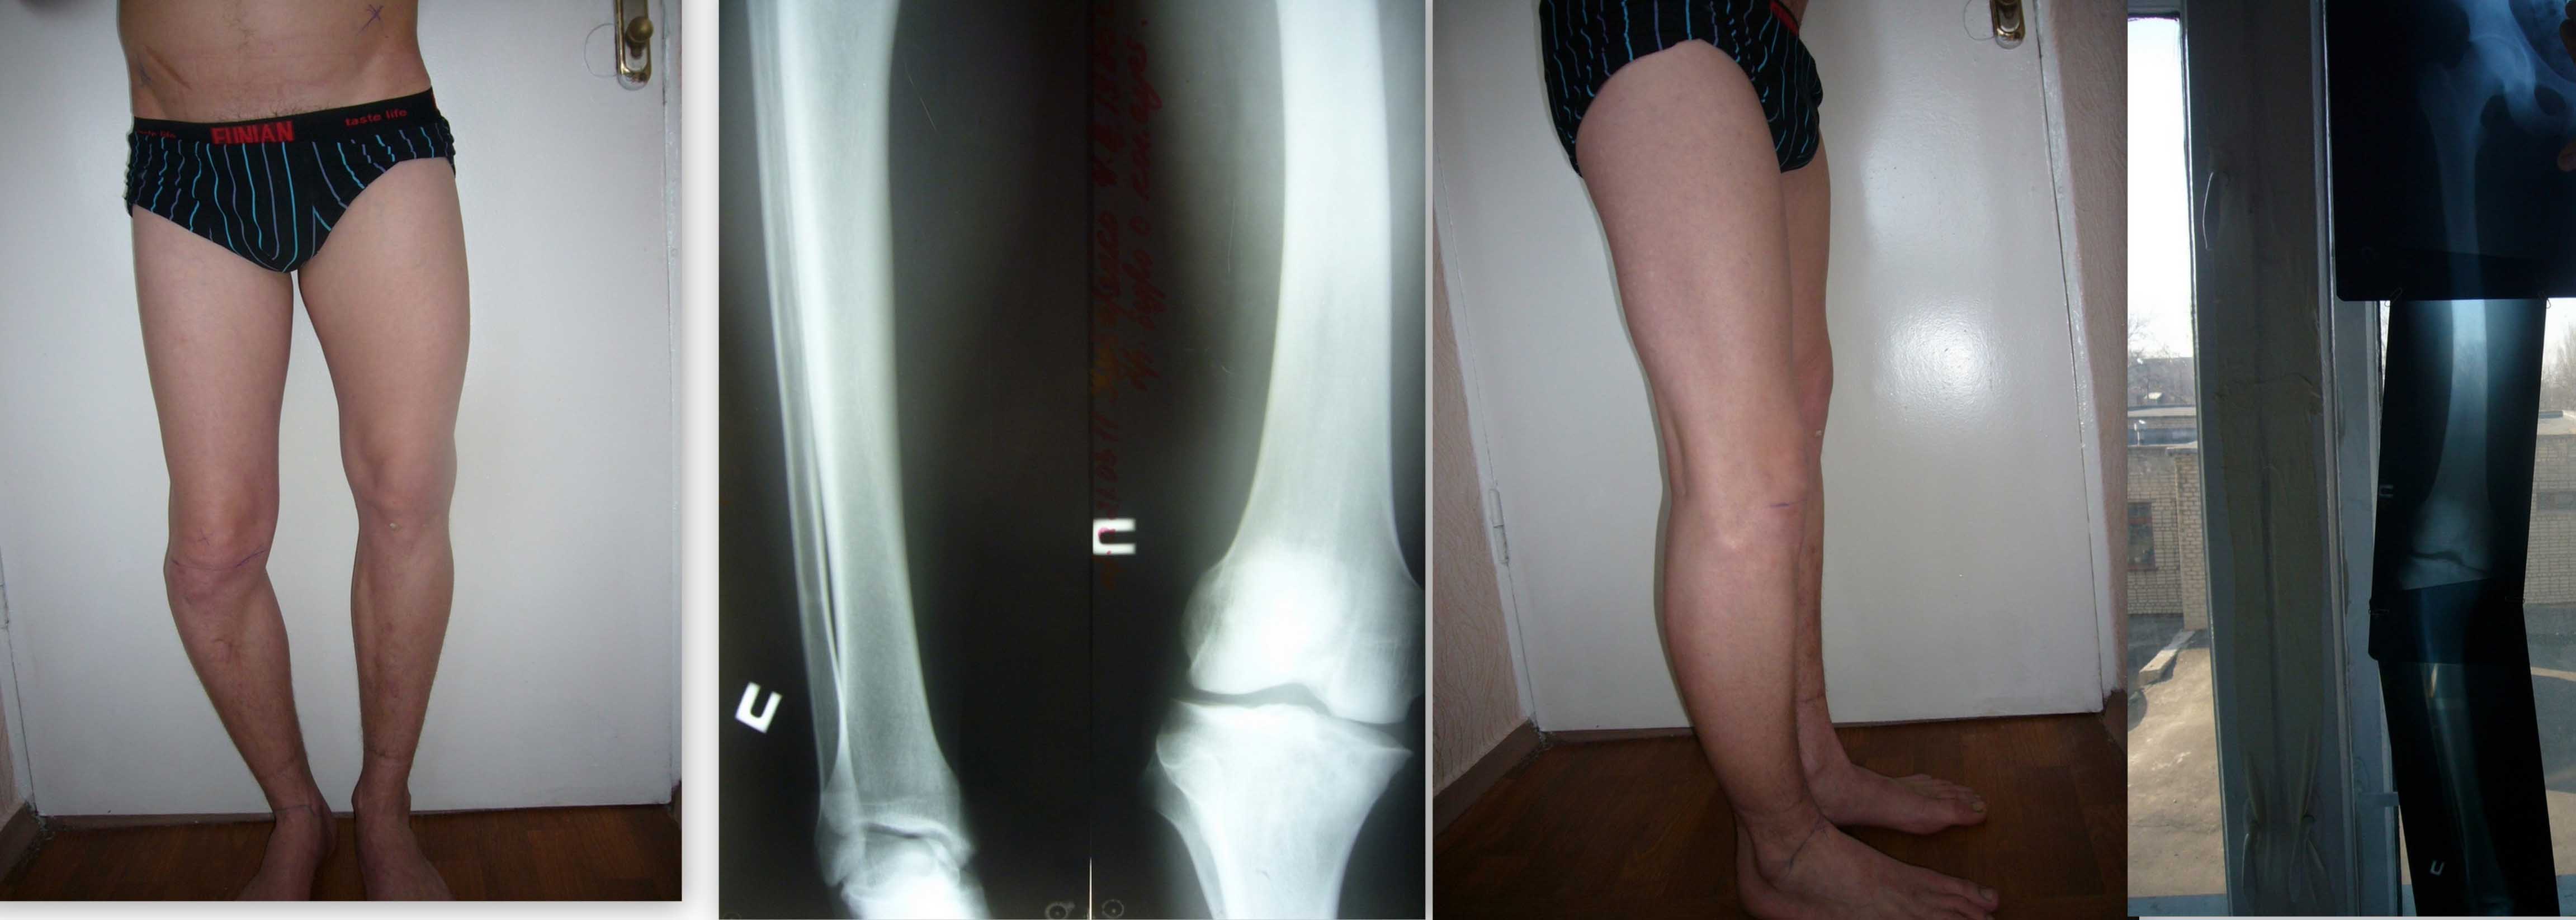

Здравствуйте уважаемые коллеги! К нам обратился интересный больной. Парень 25 лет.

В детстве перенёс гематогенный остеомиелит правой голени и бедра. До 5 лет частые флегмоны бедер и голени.

Соматически сохранен, укорочение до7 см. правой нижней конечности.

Планируем аппаратное устранение с остеотомией голени и бедра.

Уровни остеотомии?

Одномоментное или этапное устранение деформации?

Возможные варианты компоновки АВФ